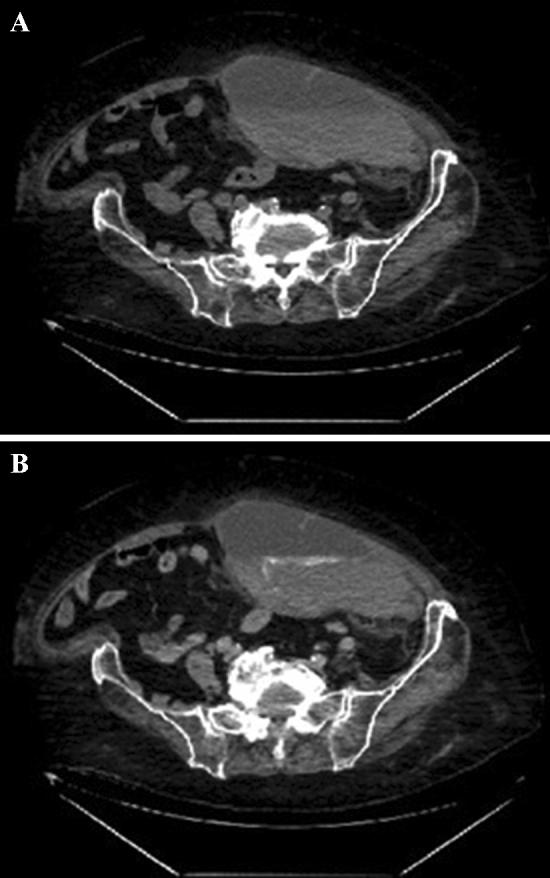

Spontaneous bleeding into the soft tissues of the abdominal and thoracic wall is described as complication of anticoagulant therapy. Computed tomography (CT) allows to detect the presence of extravasation of the contrast agent into a hematoma, which is indicated as a sign of ongoing bleeding. Other specific CT signs of such coagulopathic bleeding have been described earlier.

To evaluate the significance of specific coagulopathic CT signs for predicting the dynamics of spontaneous bleeding into soft tissues in patients with COVID-19.

A retrospective study included 60 patients with COVID-19 with spontaneous bleeding into soft tissues and extravasation of a contrast agent on CT. In addition to extravasation, a "hematocrit effect" was detected in 43 patients on CT. Of these, 39 had extravasation in the form of a "signal flare." All patients underwent transarterial catheter angiography (TCA). To assess the prognostic value of CT signs, the results of CT and TCA compared. The absence of extravasation on the TCA more often corresponded to stopped bleeding.

Extravasation on TCA found in 27 (45%) patients. The presence of the "hematocrit effect" or the combination of this sign with the phenomenon of a "signal flare" on CT (n = 43) led to more frequent confirmation of extravasation on TCA than in their absence (n = 17): 23.5% vs. 53.4% (p = 0.028).

The presence of a fluid level and the phenomenon of a "signal flare" on CT in the structure of spontaneous hematomas of the soft tissues of the abdominal and thoracic wall in COVID-19 patients more often corresponded to ongoing bleeding on the TCA. The absence of coagulopathic CT signs more often corresponded to stopped bleeding.